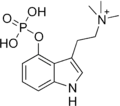

| Psilocybin | Fungi | 4-OPO3H2 | CH3 | CH3 | 4-phosphoryloxy-N,N-dimethyltryptamine | 520-52-5 |